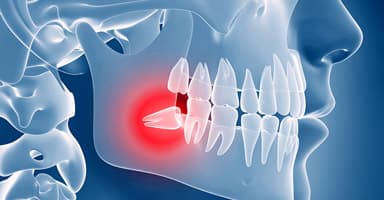

Extraction Socket

The Dental Implant Journey — from extraction to your new permanent smile

Comprehensive oral surgery including impacted wisdom teeth extraction, complex tooth removal, surgical exposure of impacted teeth for orthodontics, TMJ disorder treatment (temporomandibular joint surgery), cyst and tumor removal, and pre-prosthetic surgery. All procedures are performed under comfortable IV sedation or general anesthesia at our fully equipped Roseville surgical center. Dr. Antipov is fellowship-trained to handle even the most complex cases with precision and care.